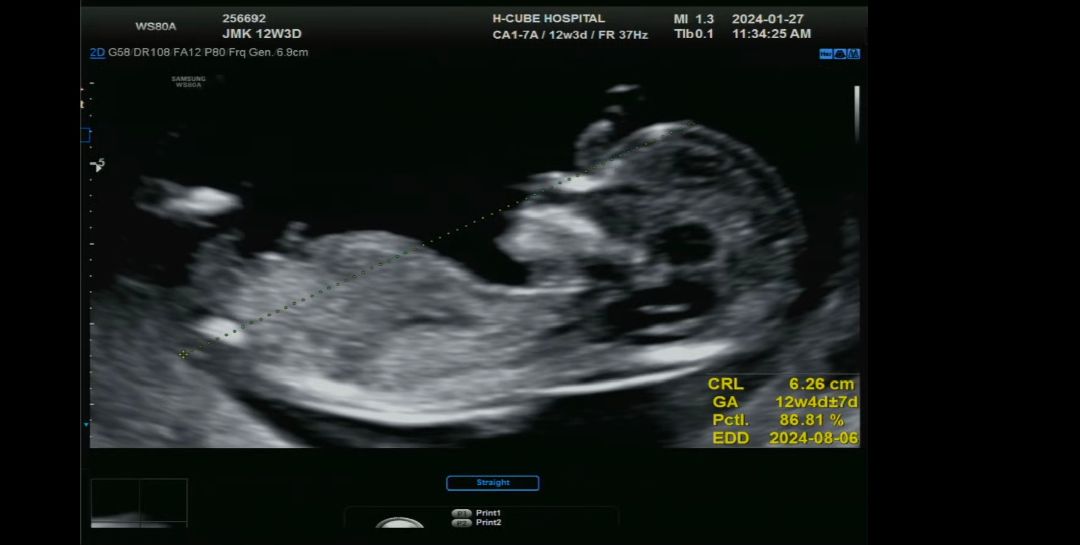

12주3일 각도법 부탁드려요!!

성별 뭐 같으신가용~~??😆😆

아들인거같은데 쪼금더 기다려보셔요~